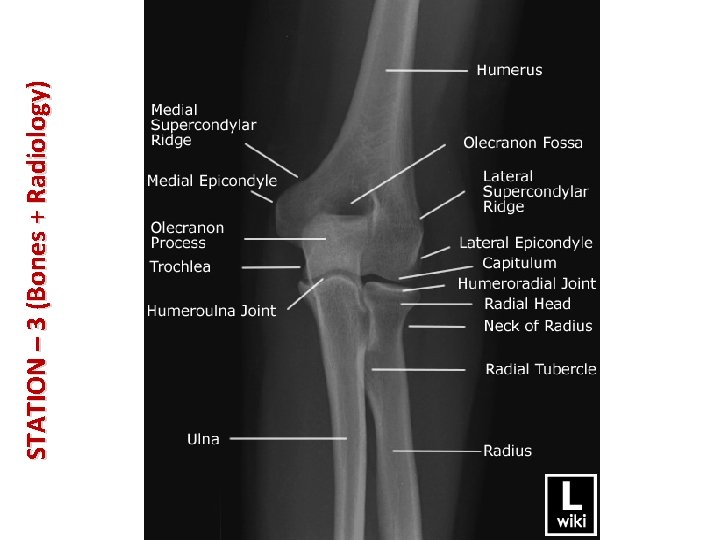

STATION – 3 (Bones + Radiology) • • The anatomical neck of the humerus is distal to its round head which is articulating with the glenoid cavity of the scapula at the glenohumeral joint (shoulder joint). The humerus has 2 tubercles: greater and lesser. Distal to these tubercles is the surgical neck of the humerus (one of the most common sites of fracture in the humerus). A fracture in this area might lead to axillary nerve damage which will result in paralysis of deltoid + teres minor muscles and loss of sensation in lateral arm. The shaft of the humerus is characterized by: – Deltoid tuberosity: point of distal attachment of deltoid muscle. – Radial groove: for the passage of the radial nerve and deep artery of the arm. Ulnar nerve (musician nerve) is passing in a groove behind the medial epicondyle of the distal end of humerus. Cubital tunnel syndrome: is a condition that involves pressure or stretching of the ulnar nerve which can cause numbness or tingling in the ring (medial half) and small fingers, pain in the forearm and/or weakness in the hand.

STATION – 3 (Bones + Radiology) • • Fractures of the humerus: – Fracture in the surgical neck: axillary nerve damage. – Mid-shaft fracture: damage to the radial nerve. – Medial epicondyle fracture: damage to the ulnar nerve. Attachments of muscles of the arm (see images below):

STATION – 3 (Bones + Radiology) • Ulna: – Stabilizing bone of the forearm. – Medial. – Longer. – The proximal end has 2 projection: • Olecranon posteriorly. • Coronoid process anteriorly: – Inferior to the coronoid process is the tuberosity of the ulna. – On the lateral side of coronoid process is the radial notch. Both of these projections form the wall of trochlear notch. – Proximally, the shaft of the ulna is thick, but it tapers, diminishing in diameter distally. – Head of the ulna has a small conical ulnar styloid process. – Note: the ulna does not articulate directly with the carpal bones. It is separated from the carpals by a fibrocartilaginous articular disc.

STATION – 3 (Bones + Radiology) • Radius: – Lateral – Shorter – The proximal end consists of: • Cylindrical head: superior aspect of the head of the radius is concave for articulation with the capitulum of humerus. The head also articulates medially with the radial notch of ulna. • Short neck: it is the narrow part between the head and the radial tuberosity. • Radial tuberosity: demarcates the proximal end (head & neck) from the shaft. – The medial aspect of the distal end of the radius forms a concavity, the ulnar notch, which accommodates the head of the ulna. – Radial styloid process is larger than the ulnar styloid process. – Dorsal tubercle of the radius lies between 2 of the shallow grooves for passage of the tendons of forearm muscles.